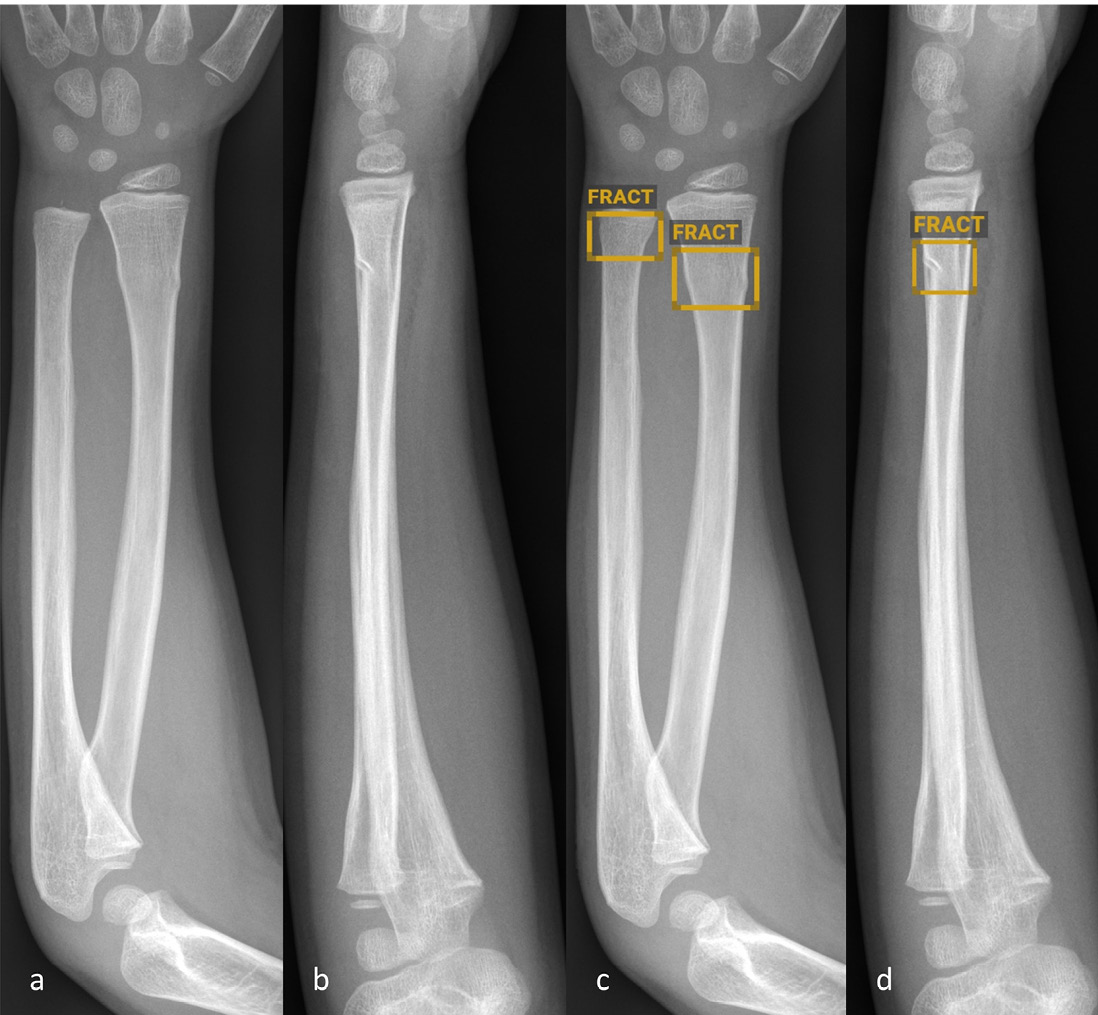

Radiographies antéro-postérieures (a et c) et latérales (b et d) de l’avant-bras d’un enfant âgé de six ans sans (a–b) et avec (c–d) marquage diagnostique réalisé par BoneView.

Figure 2: Radiographies antéro-postérieures (a et c) et latérales (b et d) de l’avant-bras d’un enfant âgé de six ans sans (a–b) et avec (c–d) marquage diagnostique réalisé par BoneView. Le logiciel d’IA a identifié et marqué correctement la fracture proximale de l’ulna, mais n’a pas détecté la luxation radiale dans le cadre de la fracture-luxation de Monteggia (encadré rouge, c–d).

© Altmann-Schneider I, Kellenberger CJ, Pistorius SM, Saladin C, et al. Artificial intelligence-based detection of paediatric appendicular skeletal fractures: performance and limitations for common fracture types and locations. Pediatr Radiol. 2024; 54(1):136–145. http://creativecommons.org/licenses/by/4.0/ La figure correspond à une partie de l’original sans autre modification.

Globalement, il existe relativement peu d’études publiées sur le diagnostic de la fracture par l’IA chez les enfants et adolescents. Les quelques études de validation réalisées en externe des logiciels disponibles dans le commerce décrits ci-dessus montrent toujours une sensibilité et une spécificité élevées (majoritairement supérieures à 90 %) des logiciels testés [4–6]. Les études varient toutefois fortement en termes de nombre total de radiographies analysées (entre 300 et 2634), de nombre de radiographies par groupe d’âge et d’évaluation des résultats. Seule une étude classe les résultats en fonction du type de fracture spécifique, mais ne tient pas compte de la localisation anatomique [6]. Dans une étude réalisée à l’hôpital pédiatrique universitaire de Zurich, nous avons récemment testé la précision diagnostique du logiciel d’IA BoneView (Gleamer) dans un ensemble de données comptant 1000 radiographies de localisations de fractures fréquentes chez les enfants (avant-bras, coude et jambe inférieure) [7]. Pour la totalité des fractures, des taux de sensibilité et spécificité similaires à ceux de précédentes publications sur le même logiciel ont été déterminés [6]. La figure 1 montre l’exemple d’une fracture en tore de l’avantbras correctement identifiée par le logiciel d’IA. Le classement selon le type de fracture a toutefois présenté d’importantes limitations. Ainsi, des fractures en flexion de l’avant-bras n’ont pas été identifiées de manière fiable. Par ailleurs, le taux de détection des avulsions de l’apophyse styloïde de l’ulna, des fractures en tore du radius proximal et des fractures de l’olécrane était nettement plus bas (< 80 %) par rapport aux autres fractures de l’avantbras. Dans la partie inférieure de la jambe, un taux de détection inférieur des « toddler’s fractures » (74 %) et fractures survenues sur trampoline (66 %) a été observé. Au niveau des coudes, seules les fractures supra-condyliennes complètes et les fractures du col radial ont été identifiées avec un taux de détection supérieur à 80 %. La détection d’épanchements articulaires au niveau du coude comme signe indirect de fracture était seulement modérée. Les luxations de l’articulation du coude n’ont pas été identifiées avec fiabilité (figure 1). Pour résumer, il est à retenir que les résultats – parfois discrets, mais extrêmement pertinents – susceptibles d’échapper à un oeil moins avisé ne peuvent pas non plus être détectés de façon fiable par le logiciel.